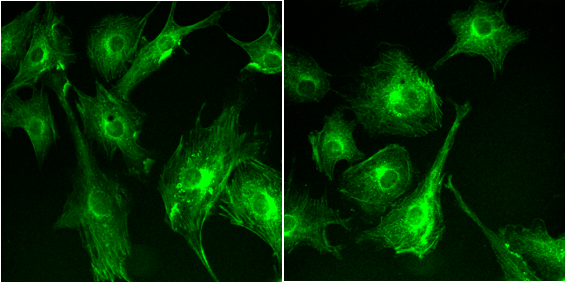

生物医学光子学领域常见应用场景如单分子观测定位、细胞核成像、细胞与亚细胞内部超微结构解析需要在极弱光条件下实现高时空分辨成像。千眼狼sCMOS科学相机凭借高量子效率、低读出噪声、高动态范围、大满阱容量特性成为必备的研究工具。

细胞及细胞核成像:sCMOS科学相机可搭载电子显微镜,采集微流控荧光微球的图像数据序列。

观测胞内运输、细胞器动态过程:sCMOS科学相机,可搭载转盘共聚焦显微镜捕获细胞内结构高信噪比荧光图像,以伪彩图像呈现线粒体、肌动蛋白等细胞器的形态和分布。